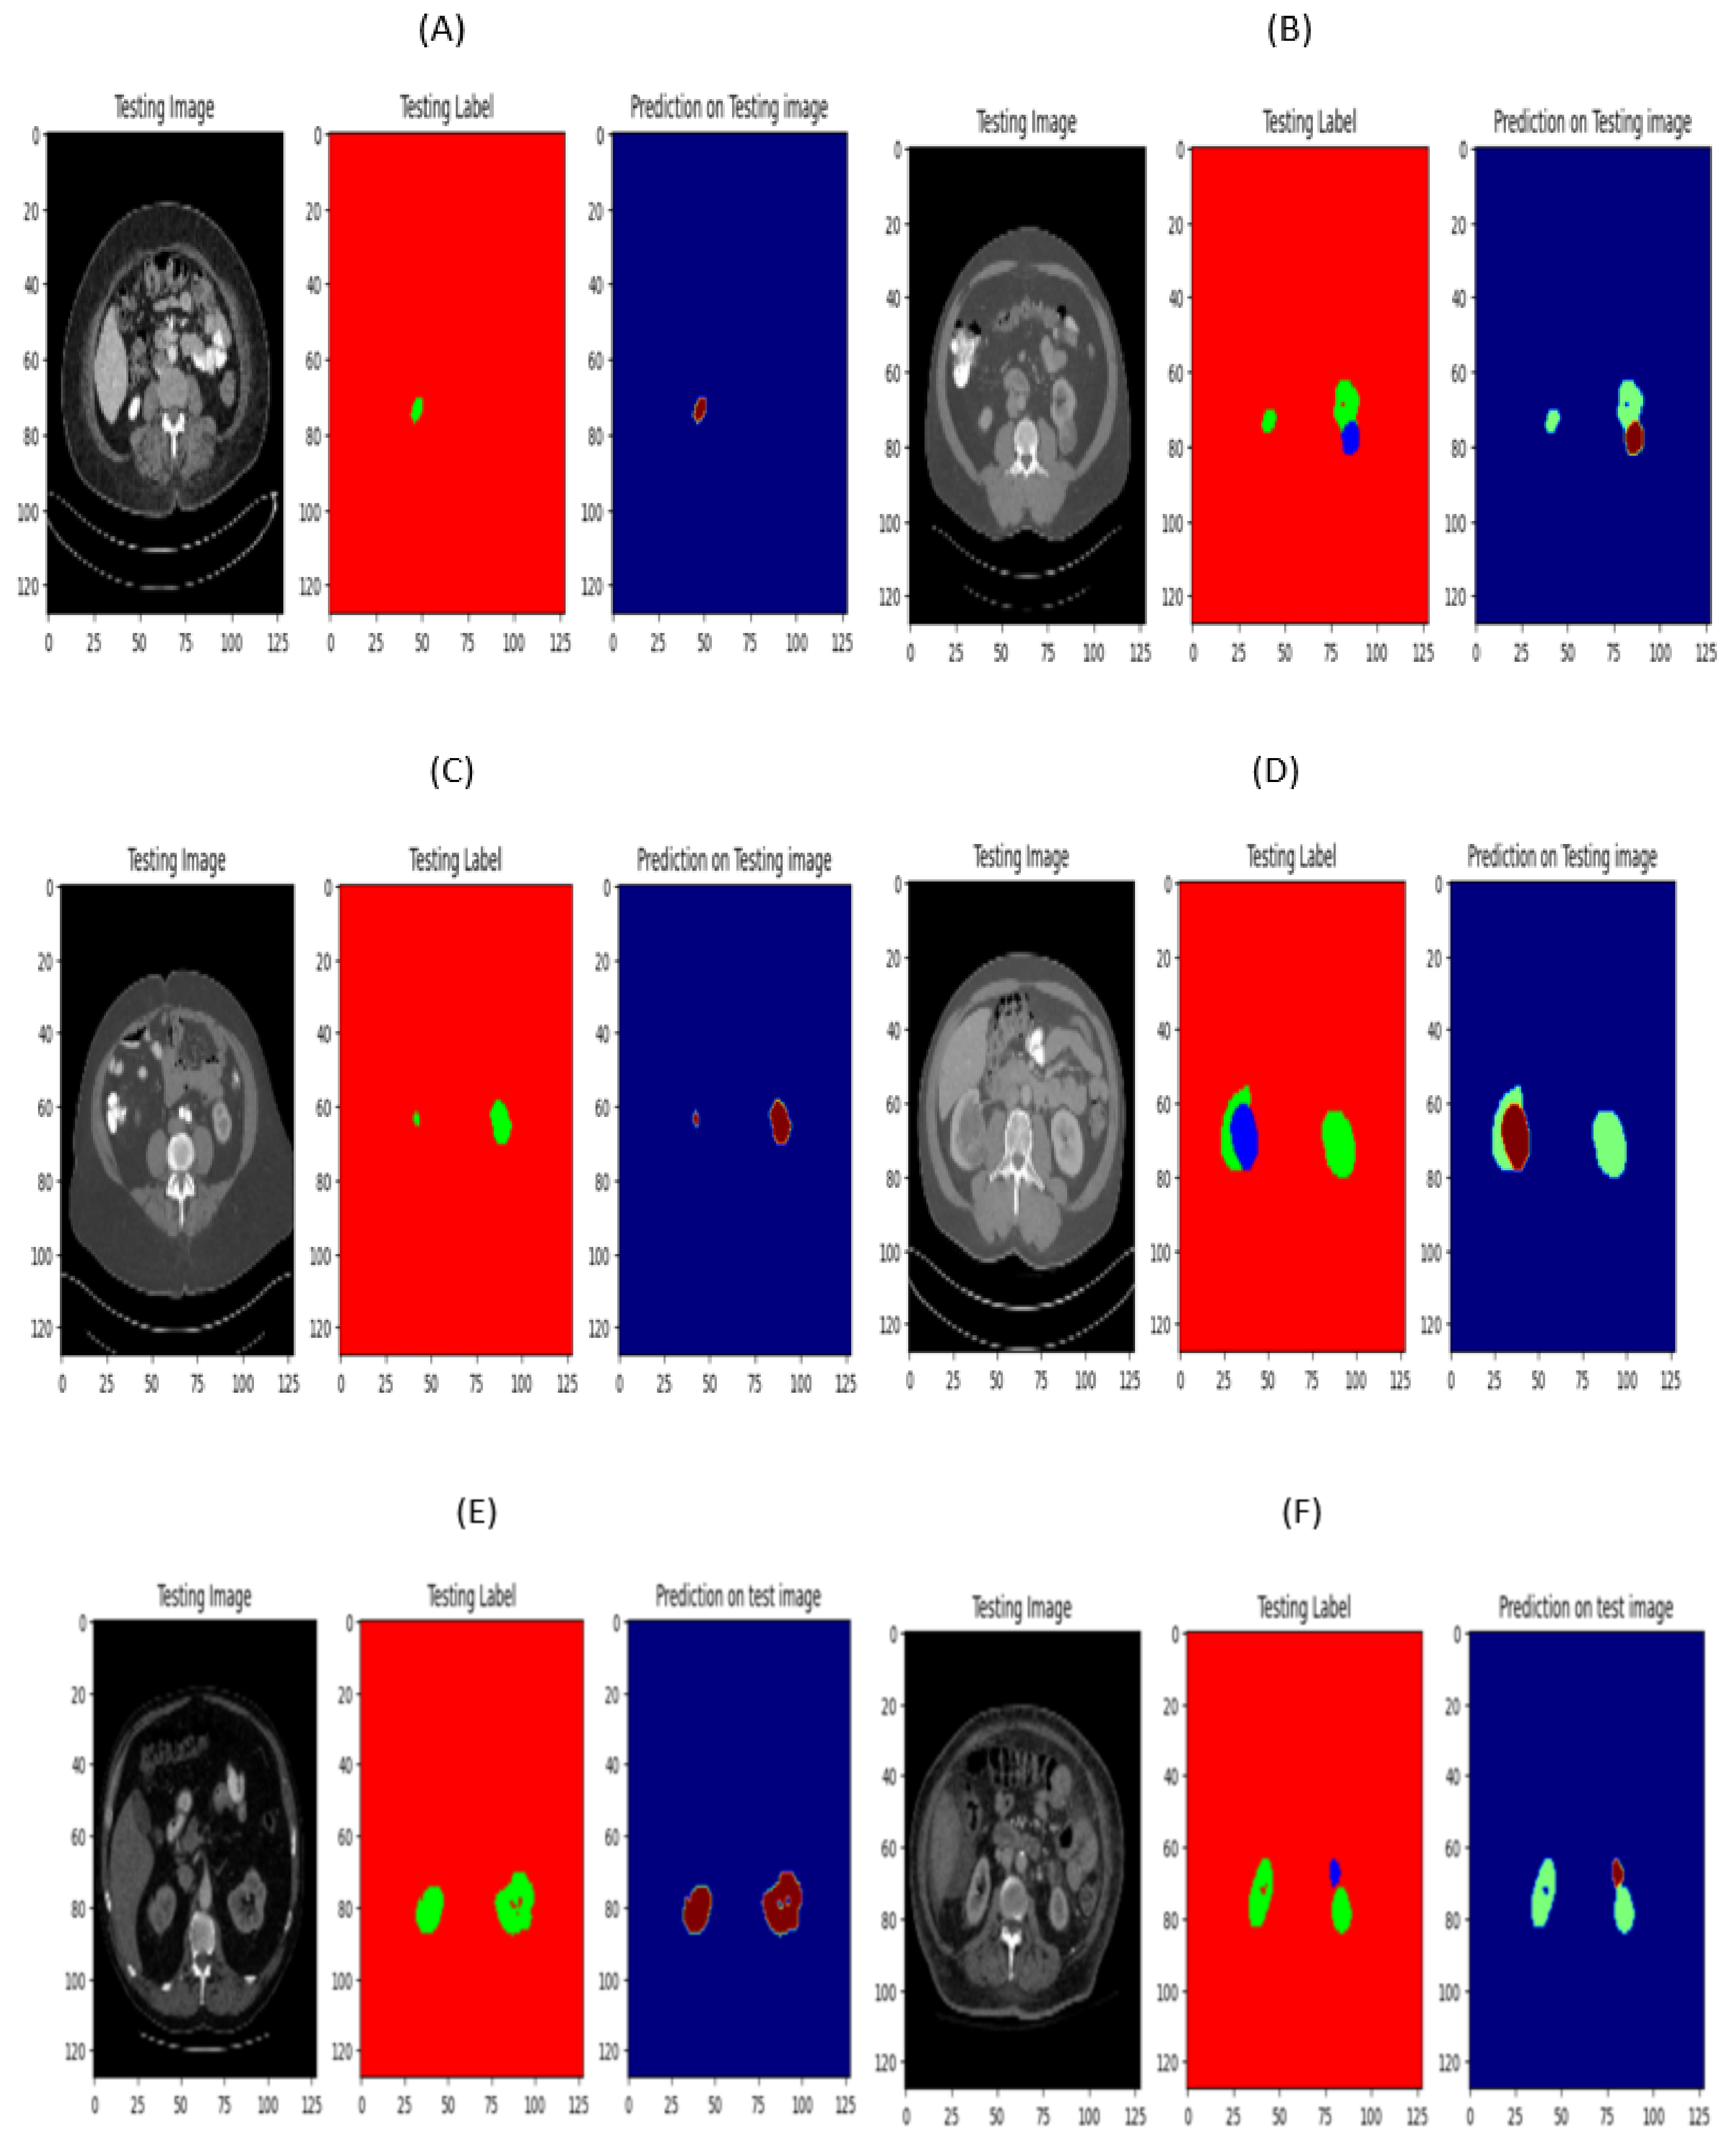

3.2.3. Prediction on Validation Images

Figure 8 presents an illustrative example of kidney and kidney tumor segmentation using the Seresnet18 and Seresnet34 models. The annotation images showcase the annotations of the kidney and tumor regions, represented in green and blue colors. These annotations serve as the ground truth for evaluating the segmentation model’s performance. In contrast, the result images exhibit the model’s kidney and tumor segmentation predictions. The predicted kidney region is green, while the tumor region is brown. The Seresnet18 and Seresnet34 model’s segmentation outputs are visually depicted in these images, clearly representing their performance in identifying and delineating kidney and tumor regions within CT scans.

Figure 8.

(A) seresnet18 image normal and (B) seresnet18 image with tumor (C) seresnet34 image normal and (D) seresnet34 image with tumor.